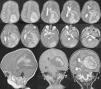

Teratoma is a common form of germ cell tumors composed of multiple tissues foreign to the site in which arise with a histological representation of all three germ cell layers. Intracranial teratomas are very rare. In this study, we report three cases of intracranial teratomas with an interesting clinical course, neuroradiology, and outcome. In addition, we review the literature and convey important messages to the neuroscience community regarding issues related to the management of these rare tumors. The present cases are interesting examples of intracranial teratoma in terms of location of the tumor and neuroimaging findings. Delay in surgical intervention may complicate the course of the disease with progressive enlargement of tumors and development of complication including hydrocephalus. Using endoscopic surgical techniques may emerge as the preferred intervention option as compared to other traditional methods. We recommend the establishment of a national and international registry for intracranial tumors.